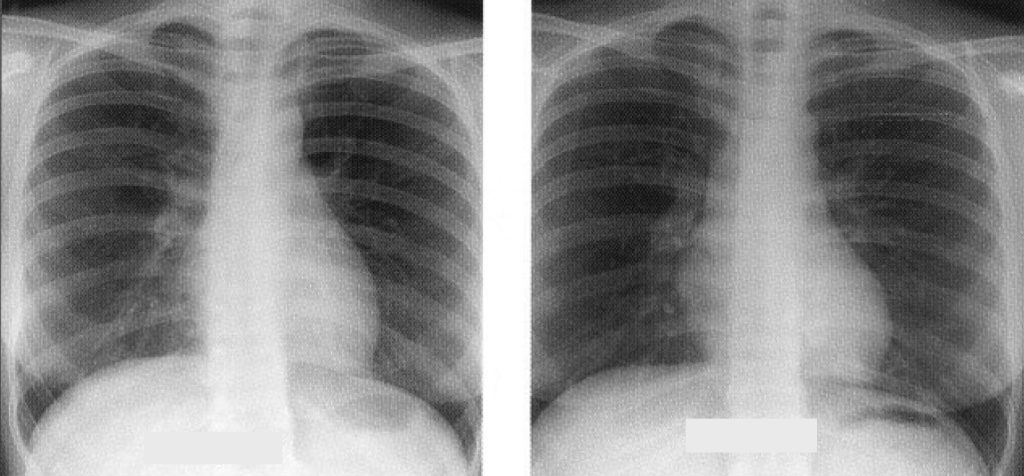

The patient was a 30-year-old nurse lady who worked as a nurse in the emergency department. She enjoyed good past health. She presented with fever, chill, dizziness, diarrhoea and malaise; together with positive SARS (severe acute respiratory syndrome) contact history. Physical examination was unremarkable. Radiologically, there was some haziness over right lung. Complete blood picture, biochemistry, cardiac enzyme andclotting were normal. In view of fever, contact history and CXR changes, the Medical Officer decided to start her on empiricallevofloxacin and ribavirin for both community-acquired pneumonia (CAP) and SARS. Upon Day 12 after admission, the patient’s fever settled and was transferred out tothe step-down ward. Then there was spike up of fever again on Day 17 after stopping all the antibiotics. Also the patient made an interesting comment. ” I felt worst after stopping levofloxacin.” At this juncture, all the investigation result was negative including corona virus serology, RT-PCR, lymphocyte count and sputum test for TB, so HRCT was ordered for her. The CT film showed the presence of centrilobular nodule over right upper lobe (RUL). As the patient had been admitted to the SARS ward before, the physician decided not for bronchoscopy. Empirical anti-tuberculosis treatment was started. Subsequently both the fever and HRCT responded well to TB treatment. A serial CXR was taken, which showed improvement over the RUL (Figure 1).

Figure 1: Serial CXRs showing improvement of RUL shadow